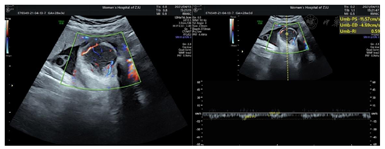

辅助检查:1.本院产前诊断超声检查示:胎位:ROA胎心:147次/分胎动:可及双顶径9.2 cm,头围32.5 cm,股骨长7.2 cm,腹围34.3 cm,胎盘:前壁GrII级,羊水指数:9.0 cm,脐动脉S/D比值2.5。备注:胎儿右侧颜面部见5.2 cm×3.9 cm×3.7 cm不均低回声,局部边界不清,内见丰富血流信号,RI:0.59;右侧上颌骨回声不规则、见回声中断,低回声与该侧上颌骨关系密切;右侧上牙槽处回声不规则、见回声中断;颈部见"U"形切迹(图1,图2,图3,图4)。诊断结果:宫内孕,单活胎,胎儿右侧颜面部不均低回声(肿瘤考虑,恶性可能),目前胎儿脐带绕颈1周。